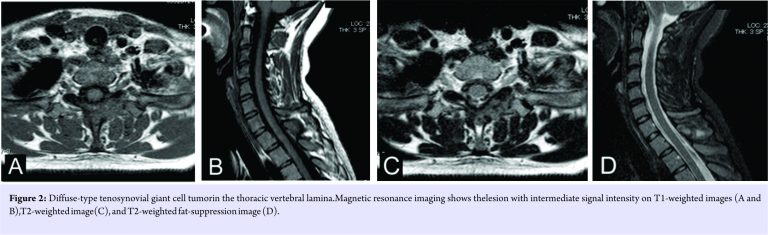

A 26-year-old woman noticed nuchal pain without any obvious cause. Plain radiographs showed no obvious findings. Computed tomography (CT) showed an osteolytic expansive lesion in the first thoracic vertebral lamina with a thinned cortex. A pathological fracture of discontinuous cortical bone was observed at the spinal process (Fig. 1).Magnetic resonance imaging (MRI) revealed a lesion with intermediate signal intensity on both T1- and T2-weighted images (Fig. 2).

Case Report: We report the case of a 26-year-old woman with D-TGCT in her first thoracic vertebral lamina. Computed tomography (CT) showed an osteolytic expansive lesion without the involvement of the facet joint. Magnetic resonance imaging (MRI)revealed a lesion with intermediate signal intensity on T1- and T2-weighted images. After computed tomographically guided biopsy, curettage was performed, and D-TGCTwas diagnosed.